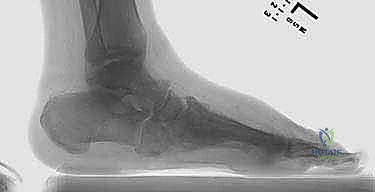

- الانهيار الهيكلي: تنهار عظام منتصف القدم، مما يؤدي إلى سقوط قوس القدم الطبيعي وتحول أسفل القدم إلى شكل محدب يشبه "الكرسي الهزاز" (Rocker-bottom deformity).

في كثير من الأحيان، يكون وتر أخيل (Achilles Tendon) مشدوداً جداً، مما يسحب الكاحل للأسفل ويزيد الضغط على منتصف القدم. يقوم الدكتور هطيف بإجراء تطويل لوتر أخيل (TAL) لتقليل الضغط الميكانيكي على مقدمة ومنتصف القدم.